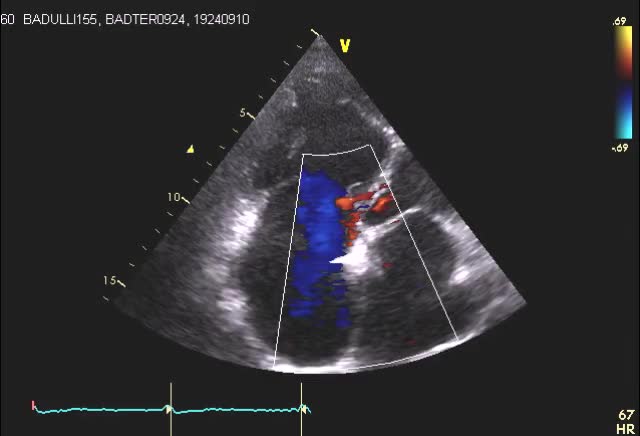

Studio ecocardiografico 2D e 3D dell’insufficienza tricuspidale funzionale e degenerativa

Luigi Badano

Insufficienza tricuspidale severa

Daniela Torta